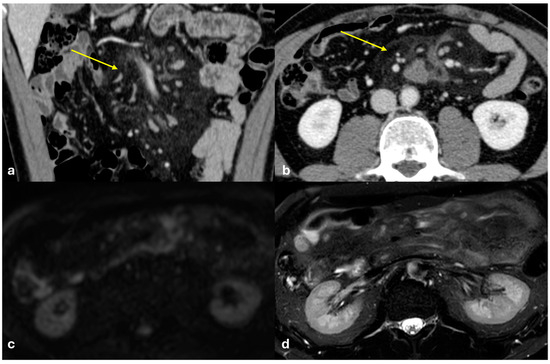

3.4.3. Splenosis